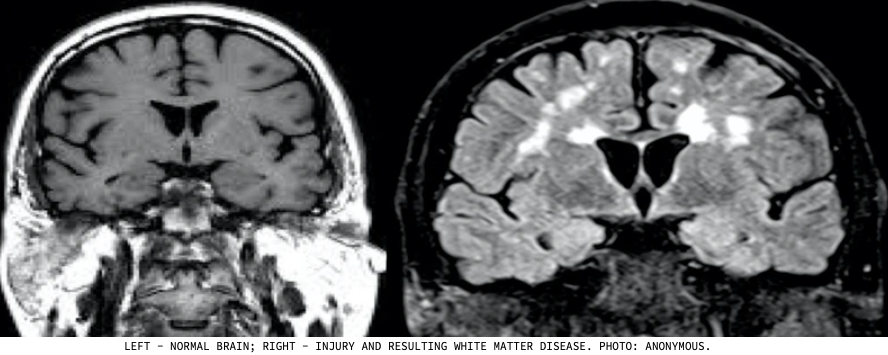

In an interview with Vice, Garry Nolan explained that the brains of people who had witnessed UAP show signs of damage that appears on scans in a similar way to multiple sclerosis.

A normal brain scan verses a brain scan of someone with MS

When we use MRIs to look at the brains of people with certain conditions like multiple sclerosis, we can see something called white matter disease. This shows up as white blobs on the MRI, and it's basically scarring or dead tissue. It happens because the immune system mistakenly attacks the brain.

Nolan noticed something interesting when studying the brain scans of UAP experiencers. Initially, they thought there was damage in a specific part of the brain that controls essential functions like movement. However, upon closer examination, they realized it couldn't be damage because severe damage there would be fatal. Instead, they discovered these individuals had an excess of connections between certain brain structures.

Brain scans of UAP Experiencers

In simpler terms, these people had too many connections between different parts of their brains, specifically the caudate and the putamen, which are crucial for higher brain functions and motor planning. This wasn't something typically seen in the general population. Interestingly, some individuals had this unique brain pattern from an early age, as shown in MRIs from previous years. It seemed like they were born with this special feature.